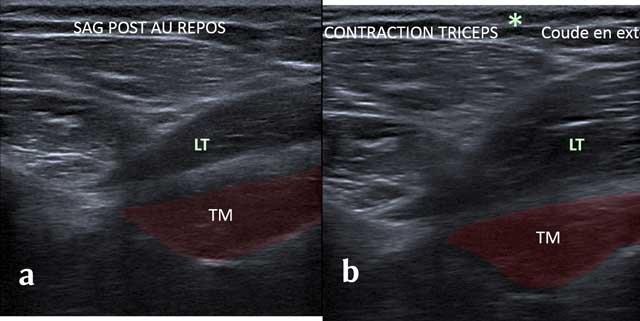

In axial cross section, the tendon of the Triceps Brachii shows the lateral edge of the Velpeau Quadrilateral Space. Adjunct tendon bundles are not identifiable. The first layer shows the Teres Minor muscle and a small triangle with the fatty axillary nerve and posterior circumflex artery. The dynamic maneuvers with tricipital contraction make the difference between the long head of the Triceps Brachii muscle of the underlying Teres Major (Figure 10).

Figure 10

Sagittal view without (a) and with (b) Tricepscontraction with elbow in extension. TM: Teres Major, LT: long head of the triceps.